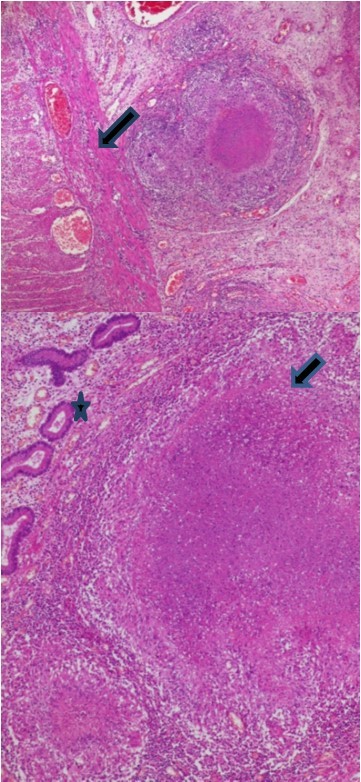

The histopathologic examination of the resected bowel specimen showedcaseating granulomatous inflammation (Figure 2), consistent with intestinal small bowel tuberculosis complicated with peritonitis and perforation (Figure 3).

Figure 2.Epithelioid granuloma and giant cells (Arrow) with caseous necrosis (Star)